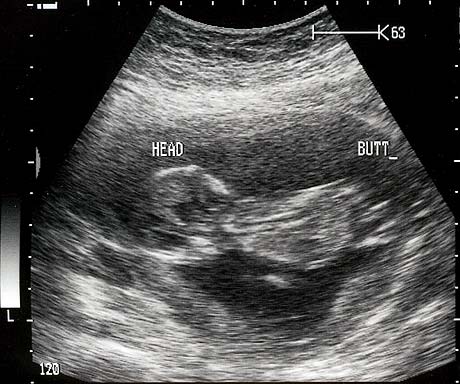

August, 2006

Baby Rockwell August 2006